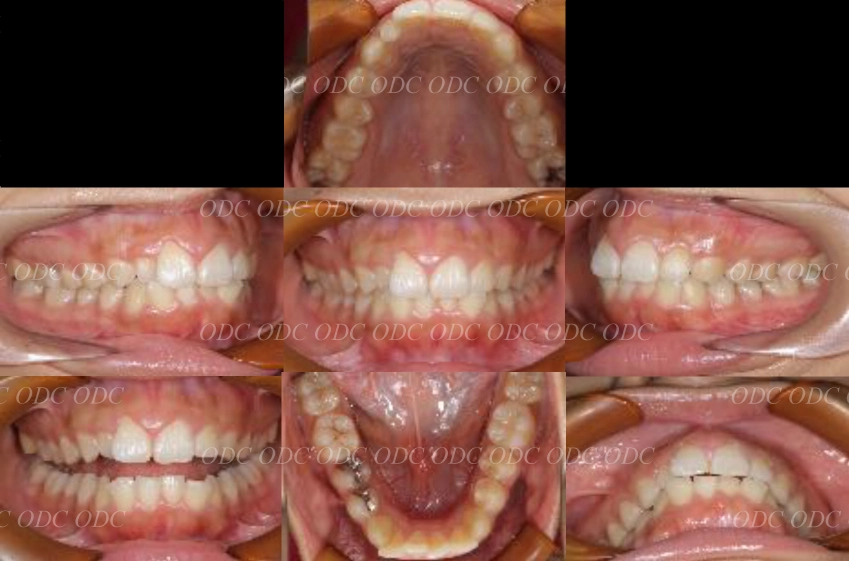

包括的治療 症例

2011年、噛めないという主訴で65歳の男性が来院されました。

全顎的な治療を希望されていましたので、口腔内はもちろん骨格・顔貌・顎関節の診断を行い治療目標を設定致しました。

上顎天然歯に関しては矯正治療、下顎にはフルマウスのインプラント治療を計画致しました。

顎関節の安定を確認した後、矯正治療とインプラント治療を並行して行いました。

約3年の治療期間を経て、計画通りの満足のいく結果を獲得することができました。

2014年、治療終了時の口腔内の状態です。

インプラント上部構造はCADCAMによって作成されたジルコニアの上部構造です。